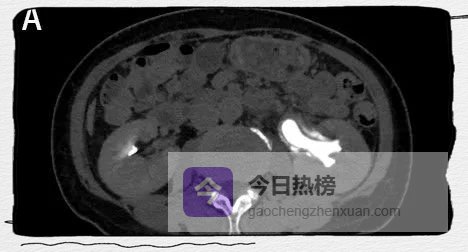

图3B

CT增强排泄期则显示内腔密度增高。